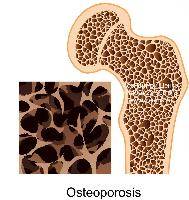

В случае перелома шейки бедра компания МосРентген Центр госпитализирует в Склиф для эндопротезирования.